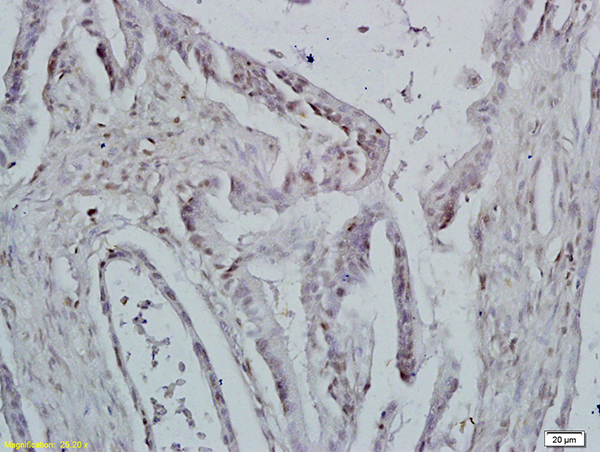

Formalin-fixed and paraffin embedded rat brain tissue labeled with Anti-ID1 Polyclonal Antibody, Unconjugated (APR05400G) at 1:200 followed by conjugation to the secondary antibody and DAB staining

Formalin-fixed and paraffin embedded mouse lymphoma tissue labeled with Anti-ID1 Polyclonal Antibody, Unconjugated (APR05400G) at 1:200 followed by conjugation to the secondary antibody and DAB staining

Formalin-fixed and paraffin embedded human colon carcinoma labeled with Anti-ID1 Polyclonal Antibody, Unconjugated (APR05400G) at 1:200 followed by conjugation to the secondary antibody and DAB staining |